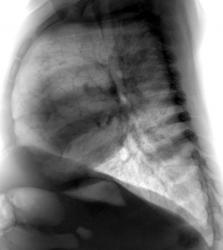

Ребёнок 1год жизни, поступил к нам в клинику с жалобыми, со слов родителей, повышение температуры до 38-39 градусов, не продолжительный мало продуктивный периодический кашель, по анализу крови лейкоцитоз и повышение СОЭ. Напрален к нам предворительным диагнозом: пневмония ? Наши снимочки:

Хотелось бы услышать мнение большинства и есть ли показания для проведение МСКТ-ОГП? В дальнейшем продемострирую более информативную картину.

Я бы расценивал представленную картину, как пневмонию. Показания для КТ? Да, хотелось бы рассмотреть тень более детально, но если течение стабильное, обычное, можно ограничиться динамикой Профессиональный раж хорошо, а как с РБ? Если необоснованно сканировать таких мелких детей, это неизбежно приведет к увеличению онкозаболеваемости.

Да, на рентгенограмме, произведенной в прямой стандартной проекции на фоне сердечной тени визуализируется "шаровидная тень", и довольно существенных размеров. Но где она, такая хорошо дифференцирующаяся на боковой рентгенограмме.

А вот по боковой рентгенограмме меня весьма сильно "смущает" задний сегмент верхнгей доли.

А тело позвонка, отмеченного желтой стрелкой не смущает?

На боковом видно неоднородную инфильтрация, малой интенсивности, если обратите внимание на позвонок, интенсивность его изменена, за счёт наложения инфильтрации:

Врача МСКТ осадили по поводу наличия опухоли или абсцесса, но ни как не пневмонии, а вот и сканы;

Как видно можно было и без МСКТ обойтись, а знал бы я такой подход к ребёнку, написал бы просто сегментарная пневмония.

На мой взгляд, обычная сегментарная пневмония, тем более, в клинику укладывается. Вот сердце немного великовато. Рекомендовала бы УЗИ.

Ещё вопрос вдогонку. Отчего это у годовалого ребенка нет грудного кифоза? Аномалия это или вариант нормы?

А как вы представляите самостоятельно стоявшего годовалого ребёнка возле стойки? Отец его просто вытянул за руки, вам же известно гипермобильность детишек.